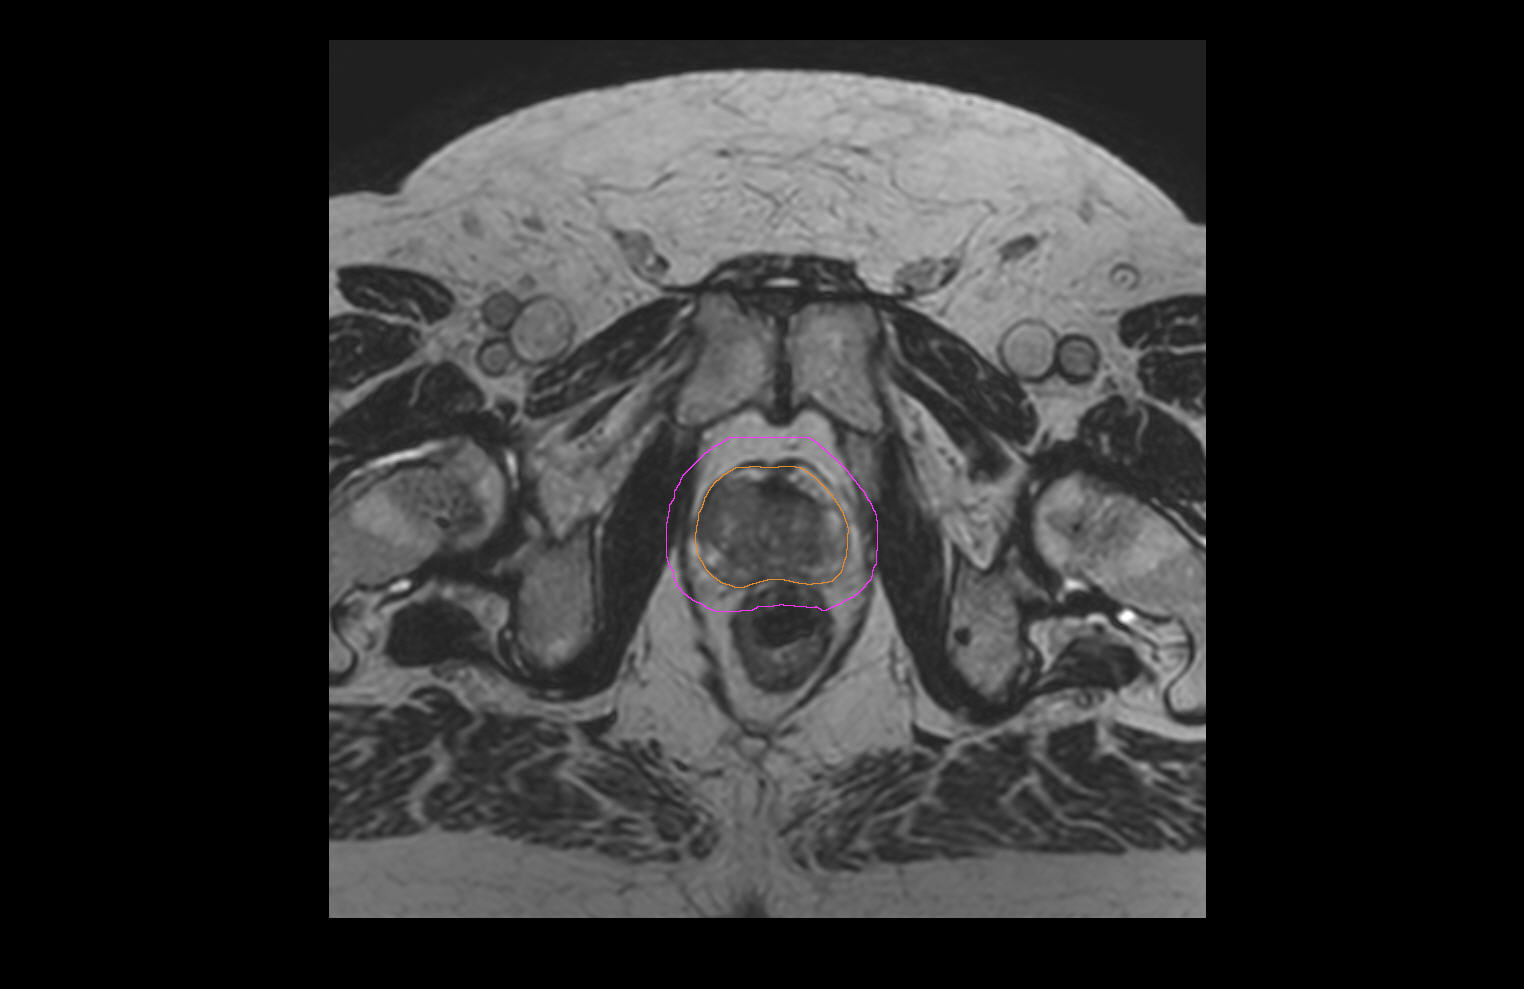

77-year-old male with prostate cancer cT3aN0M0, Gleason 8 and PSA 52 µg/L referred to androgen deprivation and radiation therapy with a prescribed dose of 50 Gy to the pelvic lymph node regions and 76 Gy to the prostate. Patient underwent MRI on Ingenia MR-RT 1.5T using FlexCoverage Anterior Coil in combination with the integrated Posterior Coil. Dose planning was performed on MRI imaging data.